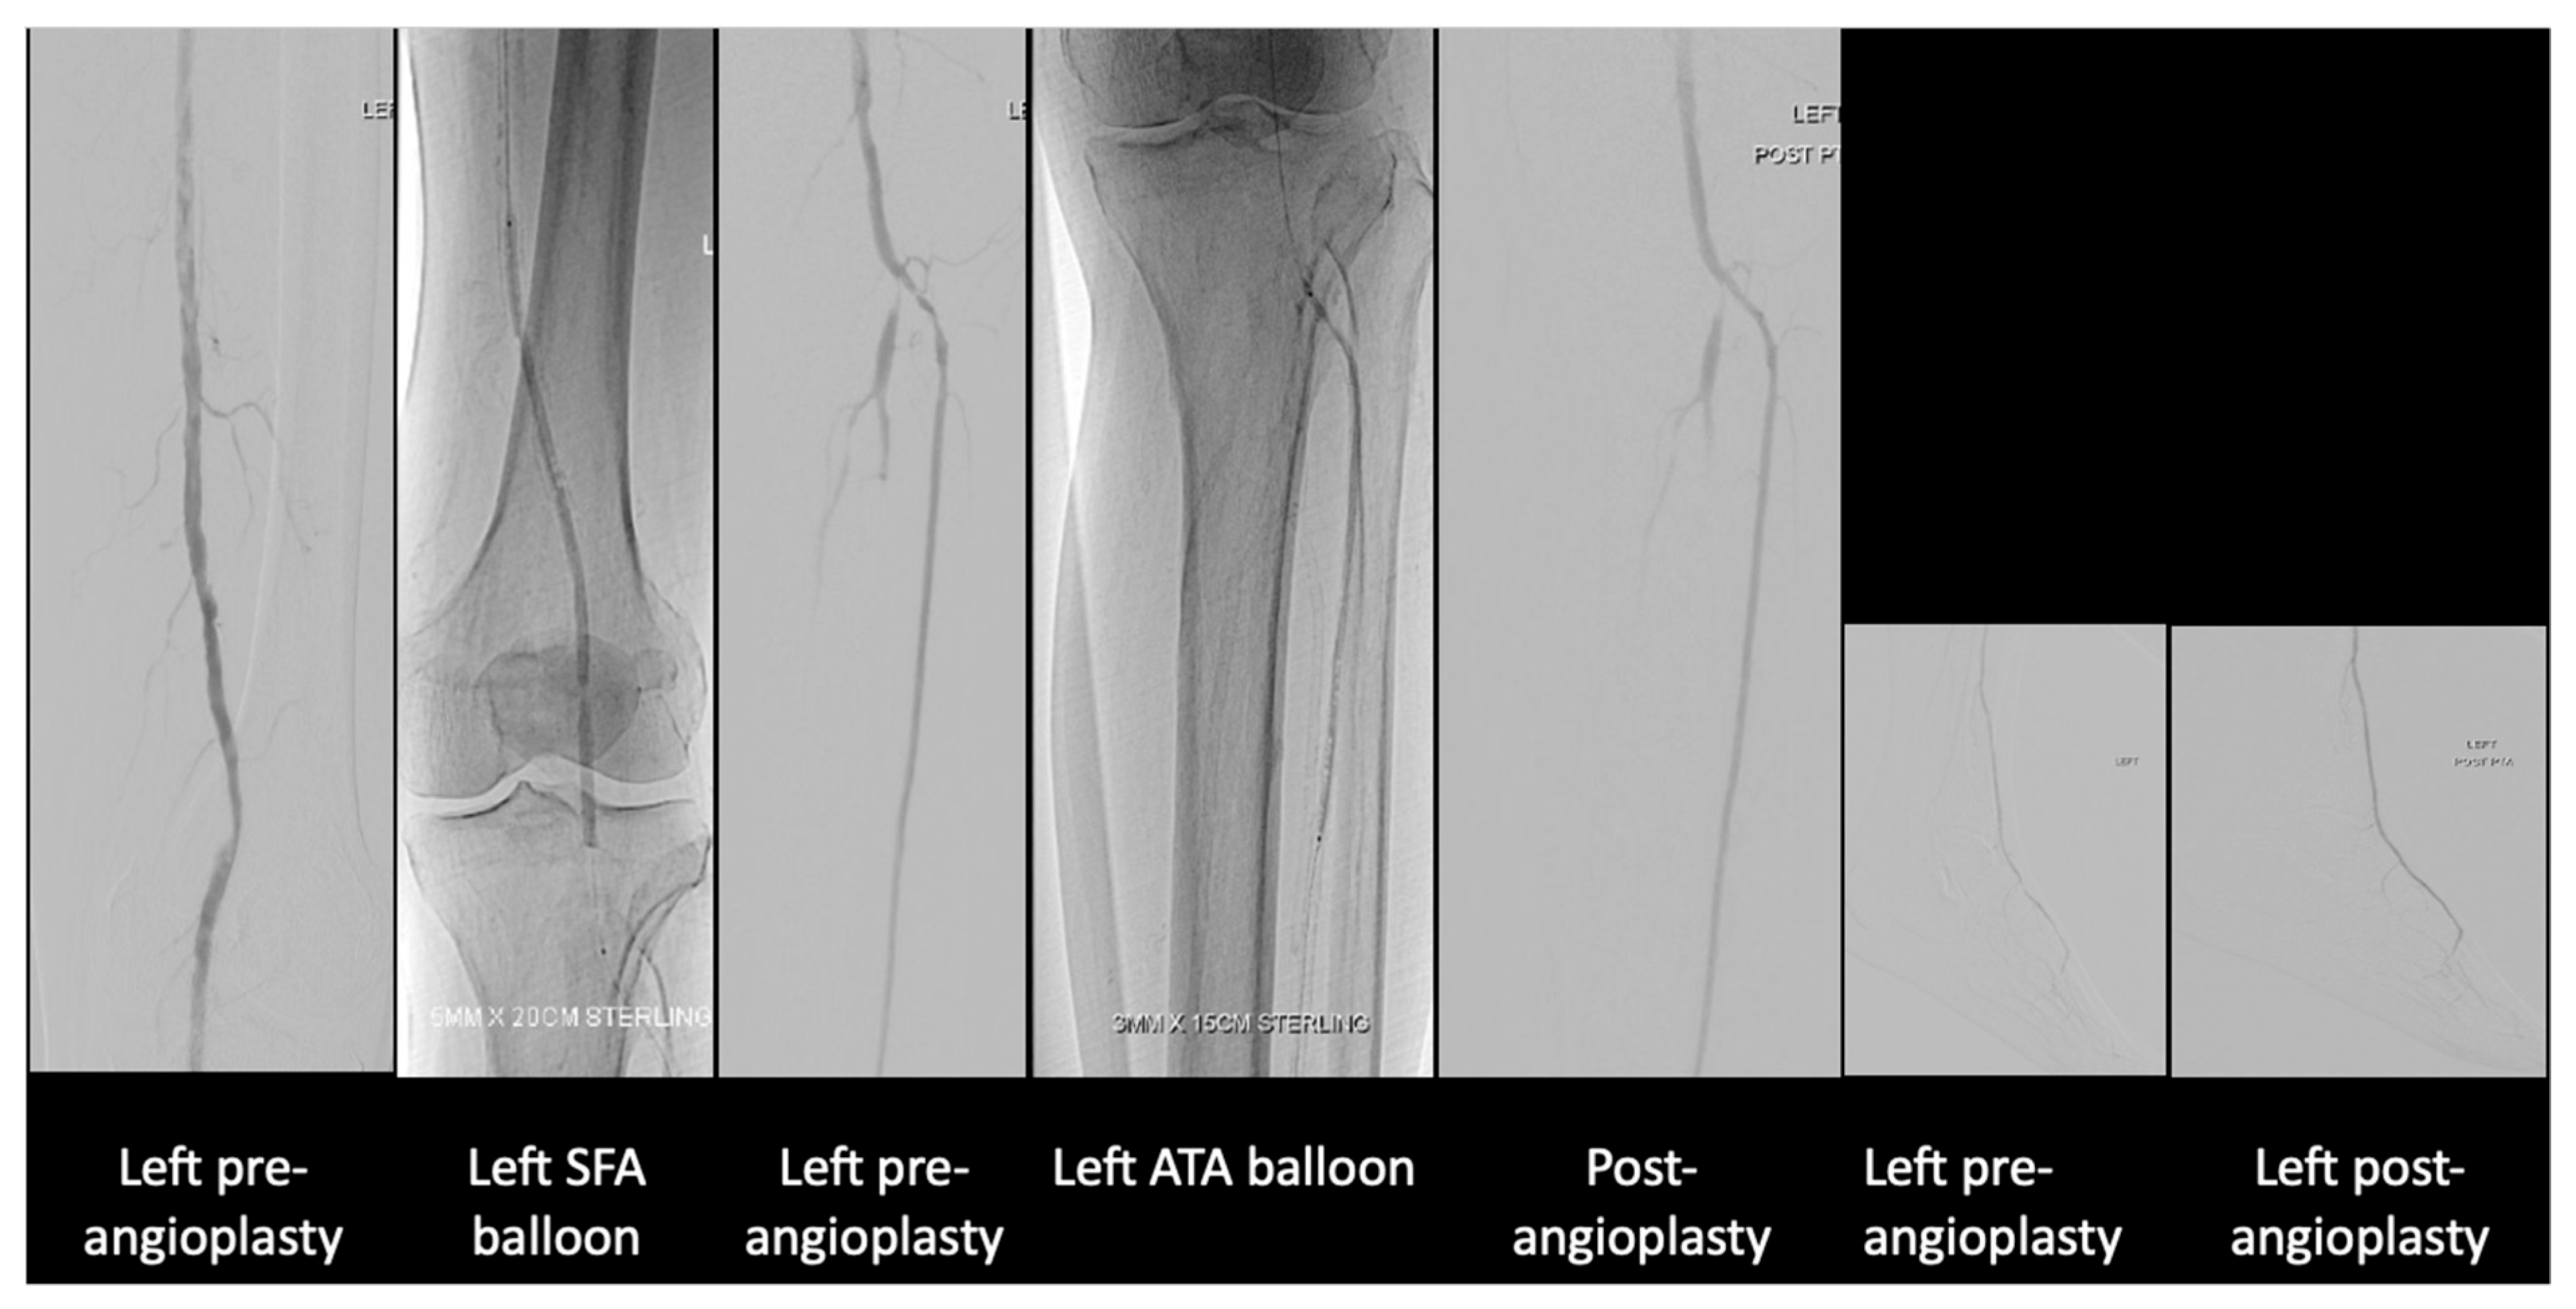

He had incidental right common iliac artery occlusion seen on staging scans for which he has complained, specifically of buttock and thigh claudication with occasional rest pain for more than 6 months. He now presents with right fifth toe and heel dry gangrene (Figure 6) associated with increased rest pain and inability to sleep at night despite multiple analgesics and opioids. His white cell count was 13 × 109/L C-Reactive protein 38.8 mg/L.

Discussion was held with his family. While they noted that his life expectancy due to his malignancy was limited, their utmost concern was him having to deal with both cancer and leg pain along with the dry gangrene. His pain could not be fully palliated with the rest pain and wound in his leg. At the same time, an upfront above-knee amputation wound may not heal given the level of arterial disease. After thorough discussion, the patient and family opted for angioplasty with stenting of his right iliac artery and angioplasty of his posterior tibial artery (Figure 7).

Figure 6. (A) Right foot dorsum view. (B) Right foot plantar view.